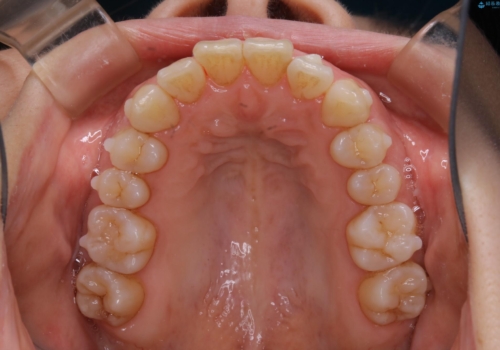

- 上下の前歯のがたつきが気になるとのことで来院されました。最短治療とインビザラインでの矯正治療をご希望されました。

前歯のがたつきを無くすためには、スペースを確保する必要があります。上の前歯のがたつきは軽度ながたつきのため、歯と歯の間を研磨をして、そのスペースを使い並べていきます。下の前歯は、1本前歯を抜いて研磨せずに、その抜歯したスペースを使い並べることになりました。

インビザライン・ライトにて矯正治療を行うことになりました。